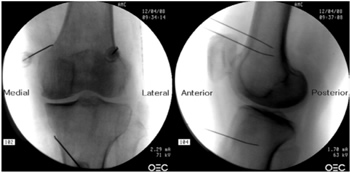

Radiofrecuencia de los nervios geniculados guiados por fluoroscopia

Para realizar una RFTNG guiados por fluoroscopia necesitamos una visión anteroposterior (AP) y lateral de la rodilla (Figura 2). Primero ubicamos al paciente en posición supina con una almohada debajo de la fosa poplítea (para que esté más cómodo) (16). Después de realizar asepsia y antisepsia de la rodilla, procedemos a ubicar los NG (Tabla II). El NGSL se encuentra avanzando la aguja de RFT hacia la confluencia de la diáfisis femoral lateral con el cóndilo femoral lateral en una visión AP y en un punto medio del fémur en una visión lateral. El NGSM se localiza avanzando la aguja hacia la confluencia de la diáfisis femoral medial con el cóndilo femoral medial en una visión AP y en un punto medio del fémur en una visión lateral. Por último, el NGIM se localiza avanzando la aguja hacia la confluencia de la diáfisis tibial medial con el epicóndilo tibial en una visión AP y en un punto medio de la tibia en una visión lateral (16,17).

Fig. 2. Proyección AP y lateral donde se observan las dianas terapéuticas usando fluoroscopia. Imagen tomada del artículo de Choi y cols. (9). Reproducido con la autorización de Jin Woo Shin.

Tabla II. Localización de los nervios geniculados guiados por fluoroscopia

Es muy importante tener una buena visión AP y lateral. En la proyección AP, la articulación tibiofemoral debe tener una anchura similar a ambos lados de la rodilla con el interespacio abierto (9). En la proyección lateral, debe existir una correcta superposición de ambos cóndilos femorales para realizar un bloqueo satisfactorio de los NGSM y NGSL (18).

La mayoría de autores toman las referencias descritas previamente para localizar estos nervios por fluoroscopia, excepto Fonkoué y cols. (18), quienes encuentran que las dianas terapéuticas del NGSM y NGSL (en una visión lateral) se encuentran en la unión del borde superior de sus respectivos cóndilos femorales con la corteza posterior de la diáfisis del fémur, y no en la mitad del espesor del fémur, como se describe clásicamente (9,10,13).

Dado que el éxito de la RFT de los nervios geniculados depende de la correcta ubicación de la punta de la aguja de RF (lo más cerca que se pueda al nervio), Know y cols. (17) demostraron con imágenes de resonancia magnética que los puntos que se usan clásicamente en fluoroscopia para la ablación de los tres nervios geniculados (NGSM, NGSL y NGIM) son correctos. Observaron que los NG pasan por la intersección formada por la línea diafisiaria y metafisiaria del fémur distal o de la tibia proximal (NGSL 92 %, NGSM 88 % y NGIM 100 %).

Después de ubicar la aguja de RFT (22G de 100 mm con punta activa de 10 mm) en los puntos deseados, procedemos a confirmar la posición del nervio utilizando un estímulo sensitivo a 50 Hz; el umbral de estimulación sensorial con el cual el paciente percibe una parestesia o dolor debe ser menor a 0,6 V. Luego confirmamos la ausencia de fasciculaciones en la extremidad inferior usando una estimulación motora a 2 Hz con 2,0 V. Finalmente se administra 2 ml de lidocaína al 2 % o mepivacaína al 2 % en cada nervio, y se inicia la RFT a 80 °C durante 90 segundos (9,14).